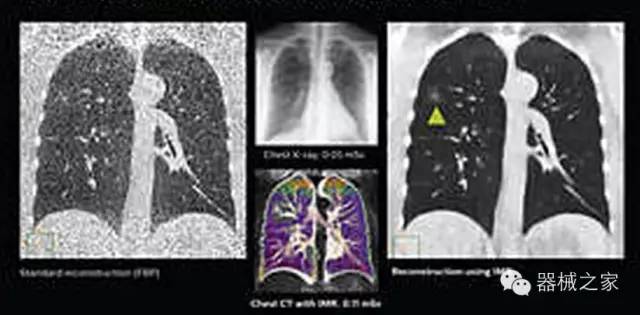

1.低劑量下的胸部顯影

透過數(shù)字化影真芯片DAS系統(tǒng)、球面微平板探測(cè)器技術(shù)和濾線柵技術(shù)等硬件技術(shù),整體提高探測(cè)器成像的能力,奠定低劑量條件下高清成像的基礎(chǔ);

應(yīng)用目前業(yè)界領(lǐng)先的新一代星光平臺(tái)iDose4 Premium及基于迭代基礎(chǔ)的O一MAR去除金屬偽影技術(shù),達(dá)成微量輻射下零偽影的高清晰成像;